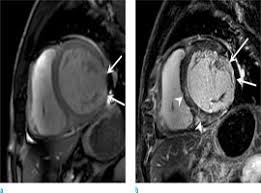

Combined Electrocardiography Coronary Angiography And Magnetic Resonance Imaging For The Diagnosis Of Viral Myocarditis A Case Report

Combined Electrocardiography Coronary Angiography And Magnetic Resonance Imaging For The Diagnosis Of Viral Myocarditis A Case Report from www.spandidos-publications.com

Journal of the american college of cardiology vol. More specifically, it is described as. Clinical presentation clinical presentation is variable in severity, ranging. Myocarditis cardiosclerosis is a pathology in which parts of the myocardium involved in inflammation die and are replaced by connective tissue. Mrt in der diagnose und monitoring neurodegenerativer erkrankungen. Khk, ischämietest bei bekannter khk). It is considered the most. Sie kann akut oder chronisch verlaufen.